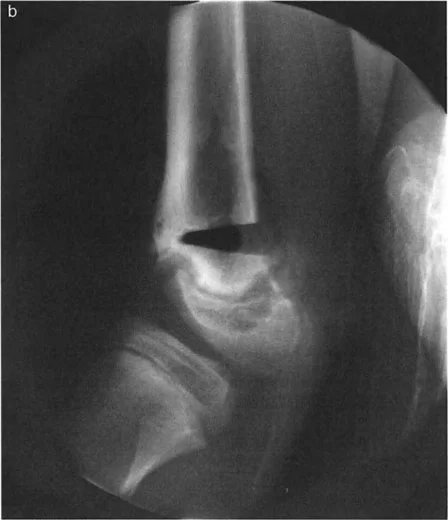

لنأخذ مثالًا سريريًا لتشوه الركبة الخلفي (recurvatum) في الجزء البعيد من عظم الفخذ. يتطلب تشوه الركبة الخلفي (وهو تشوه في المستوى السهمي حيث تفرط الركبة في التمدد) تصحيحًا دقيقًا لاستعادة حركة الركبة الطبيعية.

صورة توضح تشوه الركبة الخلفي في عظم الفخذ مع زاوية فخذية خلفية بعيدة غير طبيعية (PDFA = 108°). يظهر المريض انكماشًا في آلية العضلة الرباعية. يقع مركز دوران الزاوية (CORA) عند تقاطع القشرة الأمامية وصفيحة النمو.

في هذا السيناريو، يتم التخطيط لقطع عظم إغلاقي. بناءً على مركز دوران الزاوية (CORA)، ستعمل القشرة الأمامية كمفصل سليم.